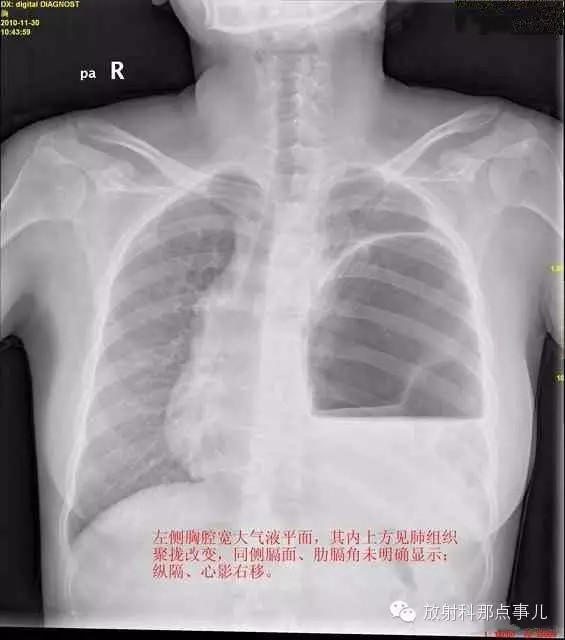

24岁,女性,腹痛渐加重并呕吐。

患者系顺产后18天产妇,产后感觉腹部疼痛不适,自认为正常反应,近两日因胸闷、腹部疼痛加剧伴呕吐来院就诊。

门诊腹部透视发现左侧胸腔巨大气液平面,为排除膈疝口服钡剂,但造影剂未见进入胃内。嘱住院,外科给予胃肠减压、补液等处理常规处理(未引流出明显气、液体)。5个半小时后再次检查,见少量造影剂进入消化道;为进一步了解情况,予泛影葡胺分别经胃管推注及口服,但均未进入胃内。当天进行外科急诊手术。

大部分胃、脾及横结肠均经过胸肋三角疝入左侧胸腔内,并见疝环形成。